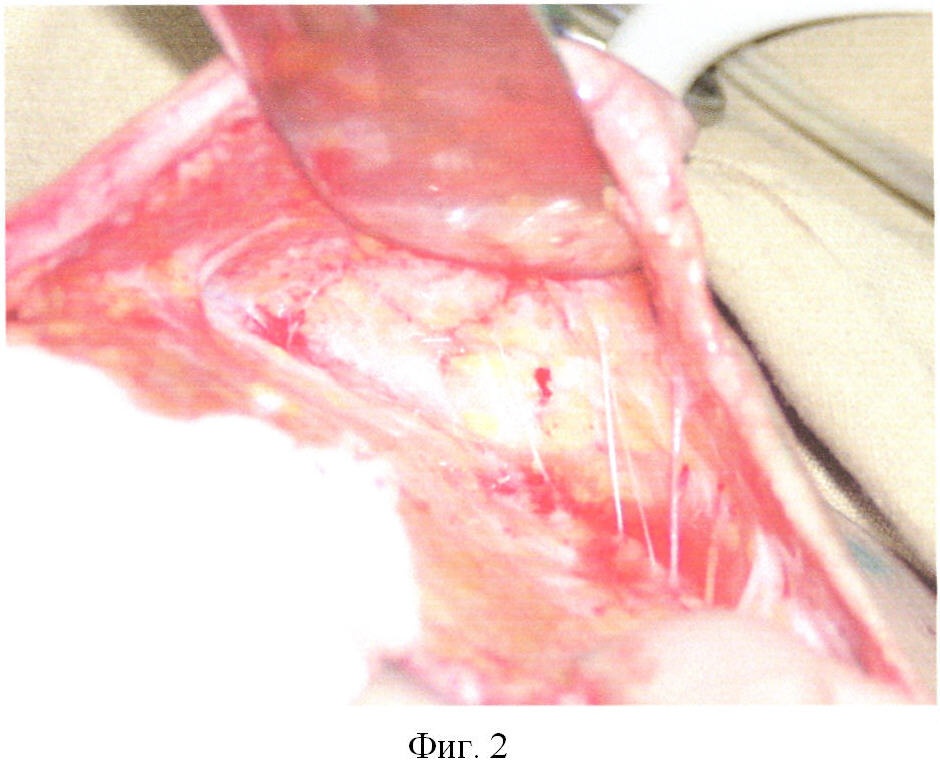

Фиг.2. Кожно-жировой лоскут и рубцово измененные ткани мобилизованы. Перфорантные артериальные, венозные и лимфатические сосуды выделены.

Больному выполнена операция: Иссечение пораженных тканей, устранение дефекта мобилизованным кожно-жировым лоскутом, т.е. в ходе операции по предлагаемому способу в подкожно-жировом слое ткани разделены путем расслоения с формированием множественных тоннелей. В перегородках между тоннелями с помощью бинокулярной лупы обнаружены и выделены перфорантные артериальные, венозные и лимфатические сосуды путем расслоения перегородок. Вокруг выделенных сосудов косовертикальными движениями браншей сосудистых ножниц и сосудистого зажима разведены мобилизуемый кожно-жировой лоскут и глубжележащие ткани, поочередно меняя расположение инструмента и направление разведения вокруг каждого обнаруженного сосуда. В результате достигнуто требуемое для перемещения тканей выделение перфорантных сосудов из паравазальных тканей с диастазом между кожно-жировым лоскутом и подлежащими тканями до 6 см.